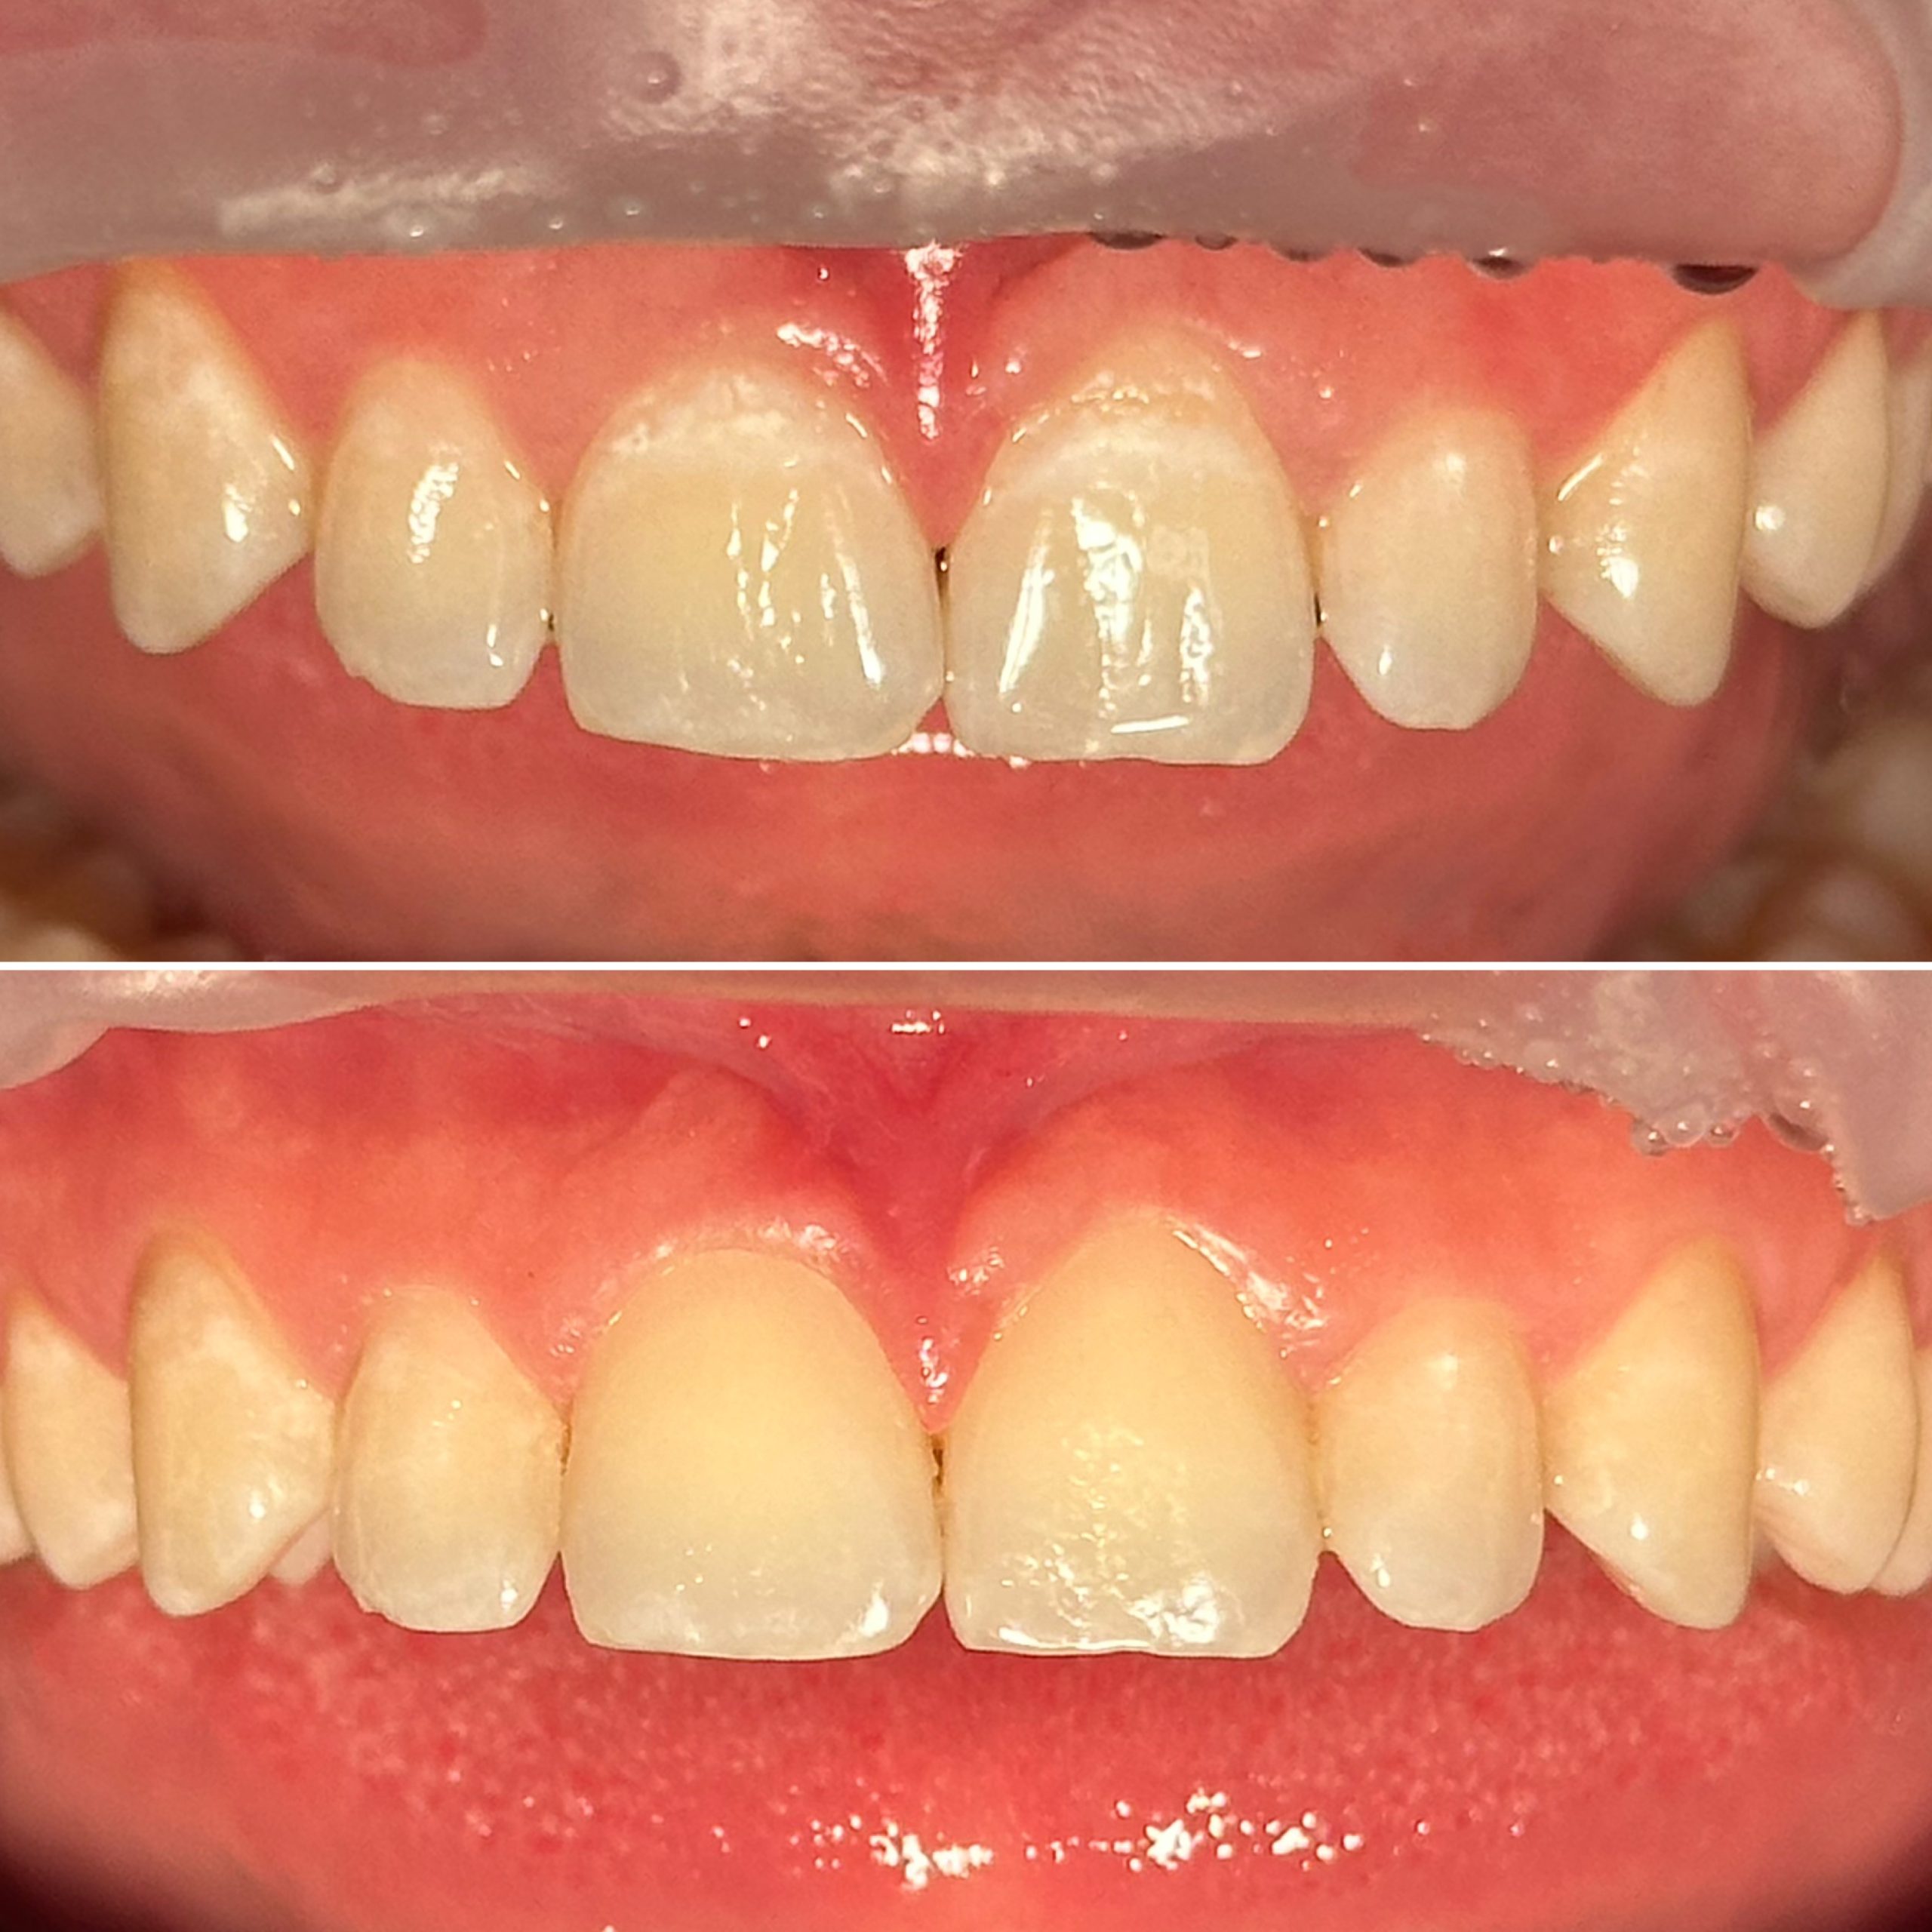

• Художественная реставрация фронтального и бокового участка зубов